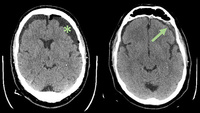

Middle meningeal artery embolization for recurrent chronic subdural hematoma

After initial evacuation of a large chronic subdural hematoma in a 67-year-old patient, recurrence led to targeted MMA embolization via radial access using SquidTM 12 (Balt extrusion), ensuring deep membrane penetration and durable treatment. [...]